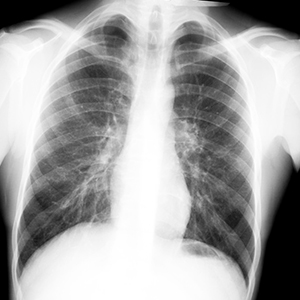

Туберкулез — инфекционная болезнь, чаще всего поражающая лёгкие, реже другие органы. Он распространен практически повсеместно. Им болеют не только люди, но и животные.

Различают открытую и закрытую формы легочного туберкулеза.

Больные открытой формой опасны для окружающих, т. к. выделяют микобактерии туберкулеза в окружающую среду. И становятся источником заражения для окружающих. Больные закрытой формой бактерии во внешнюю среду не выделяют и заразить никого не могут.

Для того, чтобы не допустить развития запущенных форм туберкулеза, в нашей стране все взрослые и подростки 15 лет и старше 1 раз в 2 года обязательно проходят флюорографию или рентгенологическое обследование легких.

Профилактикой туберкулеза во взрослом возрасте является ежегодное диспансерное наблюдение и выявление заболевания на ранних стадиях. С целью выявления туберкулёза на ранних стадиях взрослым необходимо проходить флюорографическое обследование в поликлинике не реже 1 раза в год (в зависимости от профессии, состояния здоровья и принадлежности к различным группам риска). Чтобы избежать этого коварного заболевания, следует повысить сопротивляемость организма, вести здоровый образ жизни, который включает рациональное питание, отказ от вредных привычек, занятие физкультурой, спортом, закаливание своего организма.